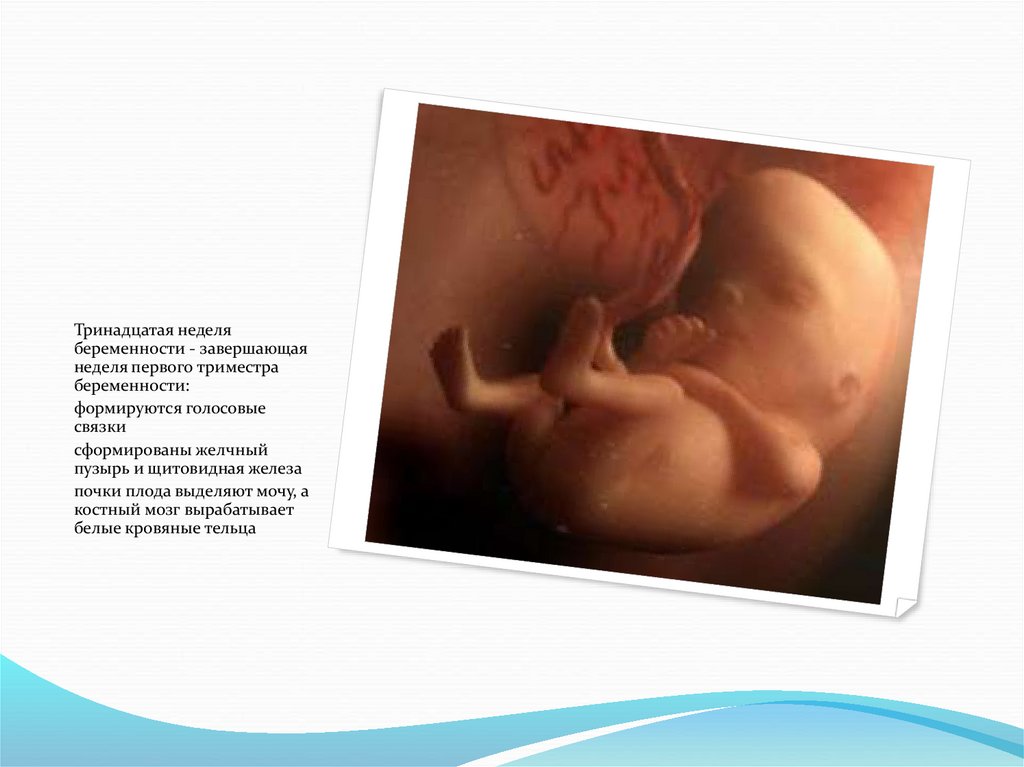

Тринадцатая неделя

беременности - завершающая

неделя первого триместра

беременности:

формируются голосовые

связки

сформированы желчный

пузырь и щитовидная железа

почки плода выделяют мочу, а

костный мозг вырабатывает

белые кровяные тельца